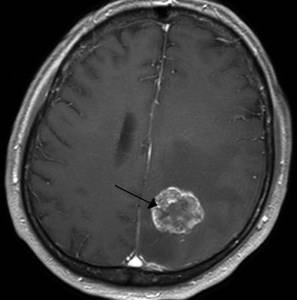

Злокачественная опухоль

Описание

Злокачественная опухоль представляет собой патологическое новообразование, состоящее из раковых клеток, которые быстро растут и способны метастазировать, что угрожает жизни человека.

Тип боли

Интенсивность и характер болевого синдрома зависят от локализации опухоли, стадии заболевания и индивидуальных особенностей пациента.

Другие проявления

На ранних стадиях опухоль может не проявляться, пока не начнет интенсивно расти. В этот момент состояние пациента ухудшается, могут возникать тошнота, утомляемость, рвота, нарушения слуха и зрения, трудности в распознавании речи, а также расстройства общей и мелкой моторики.

Клиническая картина рака разнообразна и сложна.

Методы диагностики и терапии

Диагностика включает комплексное обследование: КТ, МРТ, рентген, лабораторные анализы, гистологию и цитологию. Лечение обычно хирургическое, с возможным назначением курса химиотерапии или лучевой терапии, а затем длительного медикаментозного поддерживающего лечения.